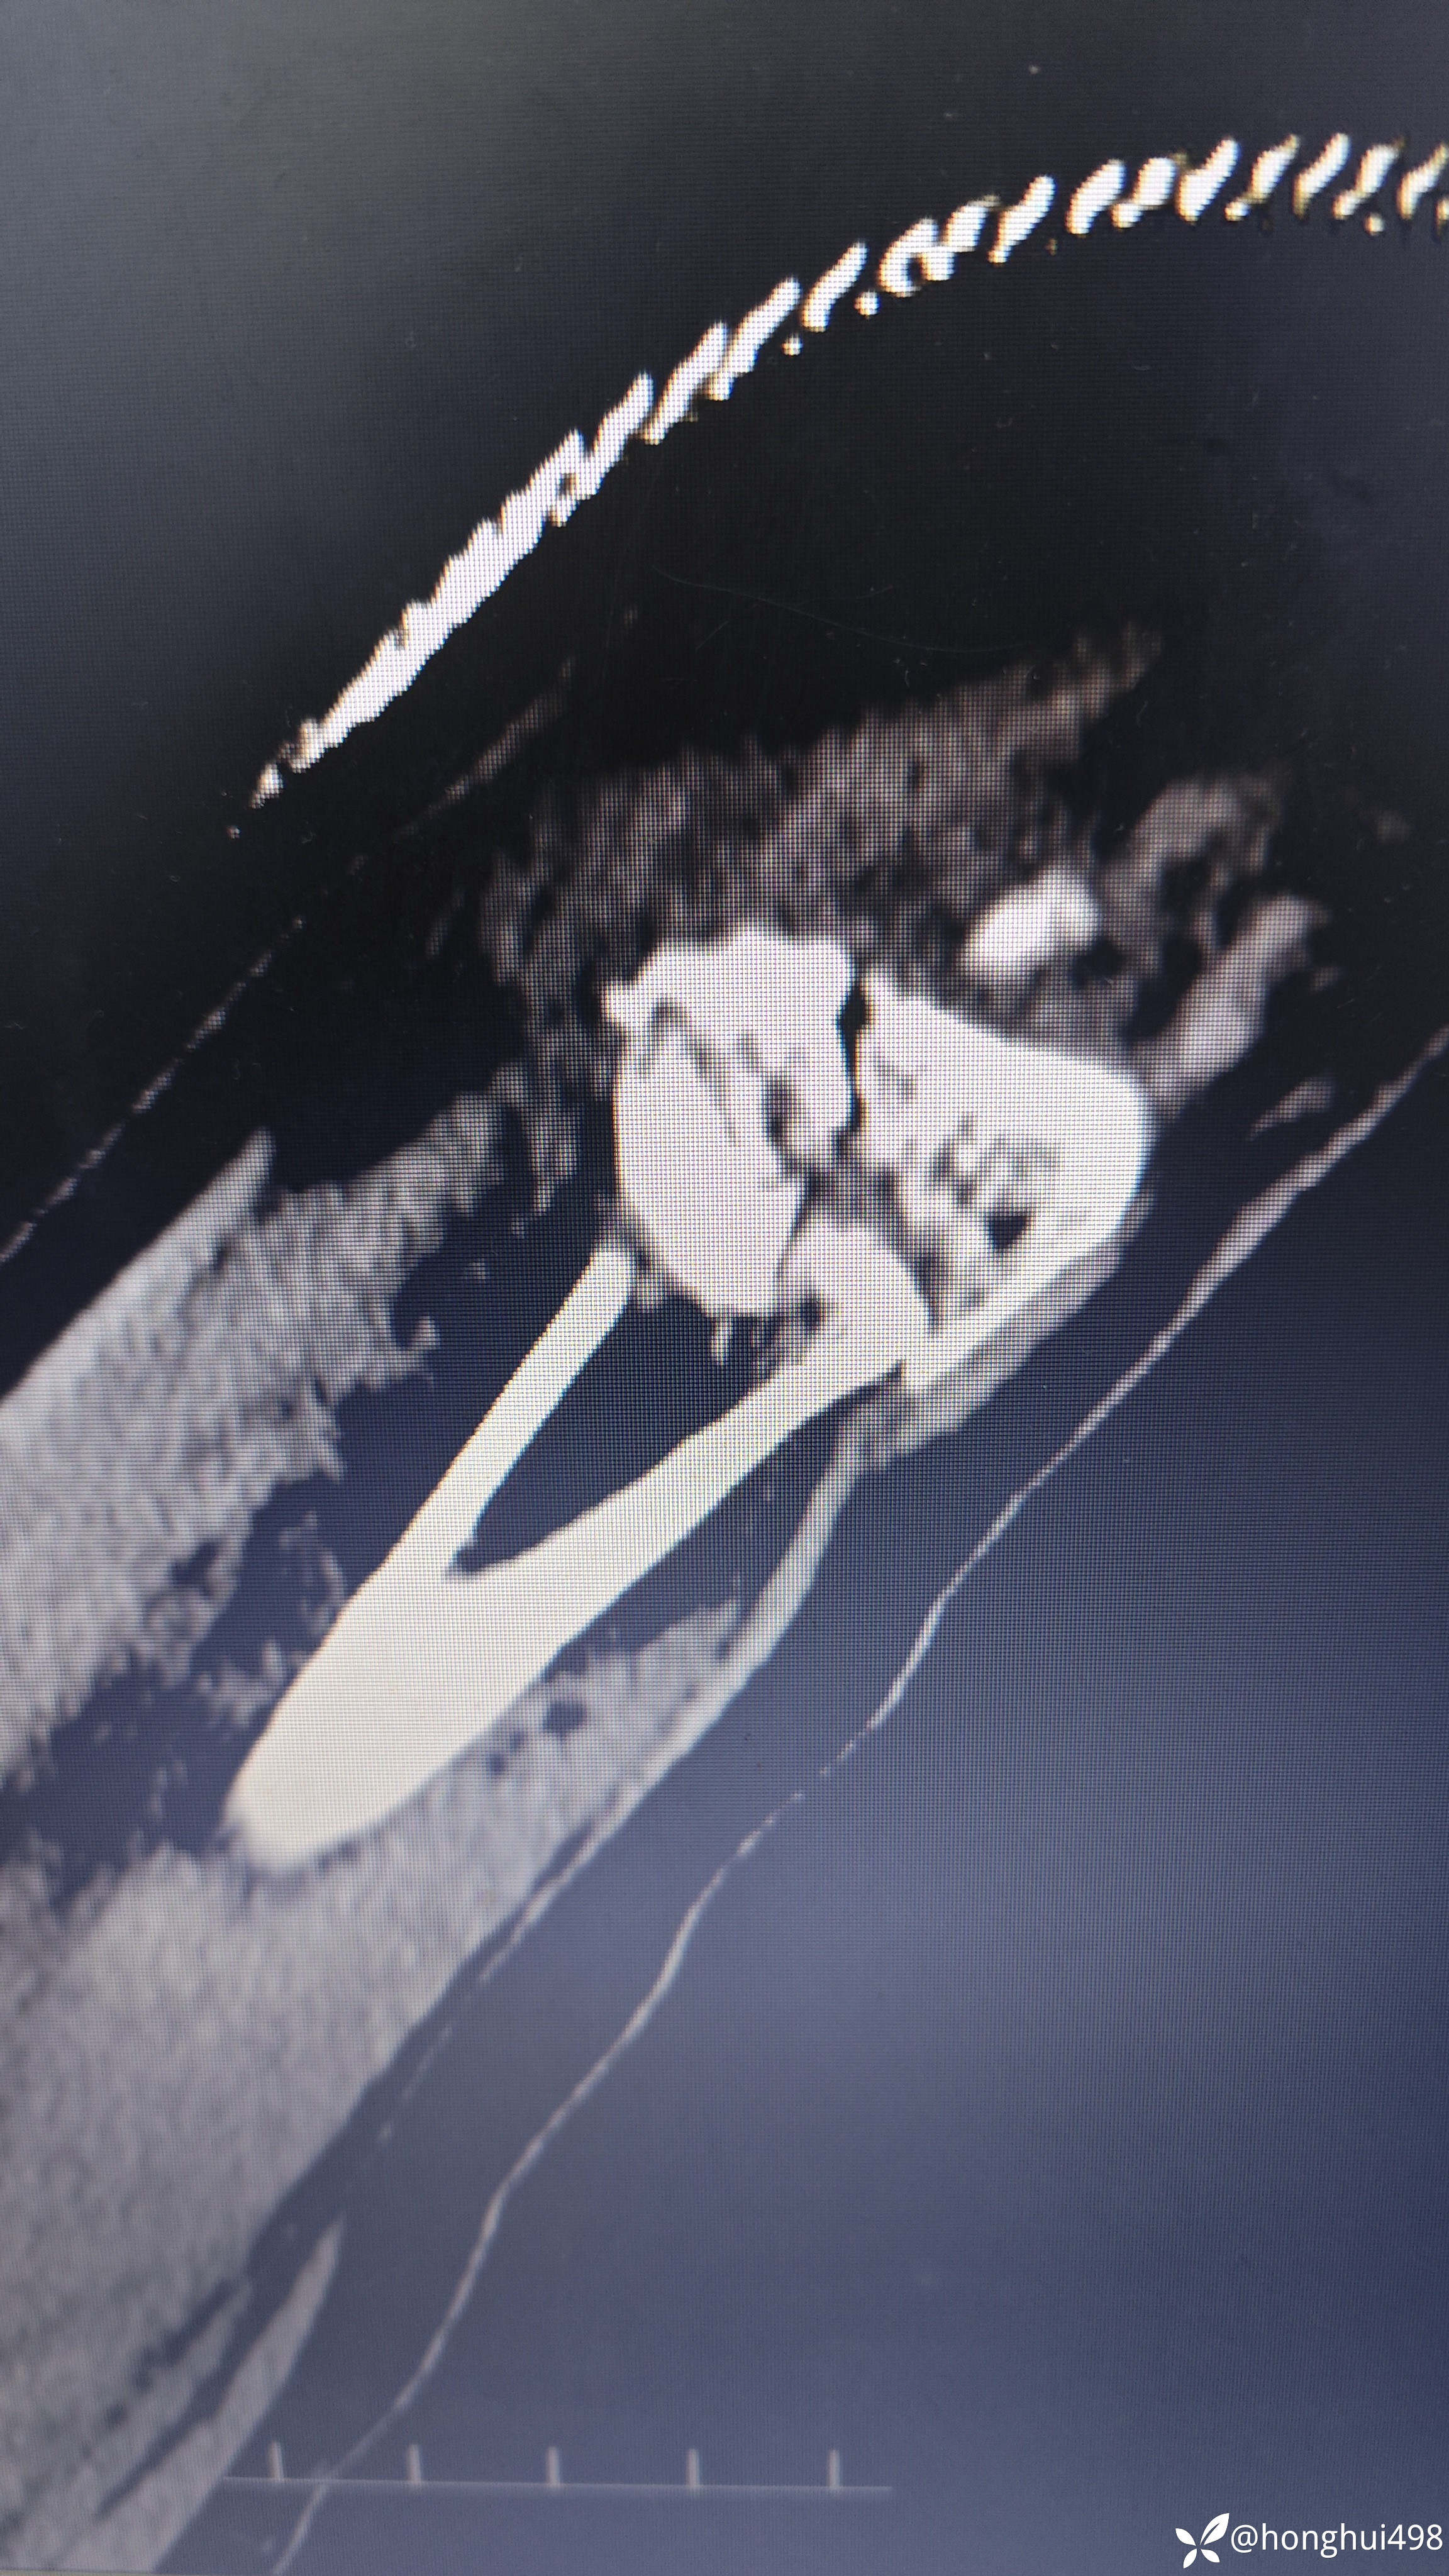

女性患者,49岁,因在家行走不慎滑倒受伤,右腕部畸形,肿痛活动受限1小时入院。入院诊断:右桡骨远端骨折。尝试手法整复失败,臂丛麻醉下行切开复位钢板内固定术。